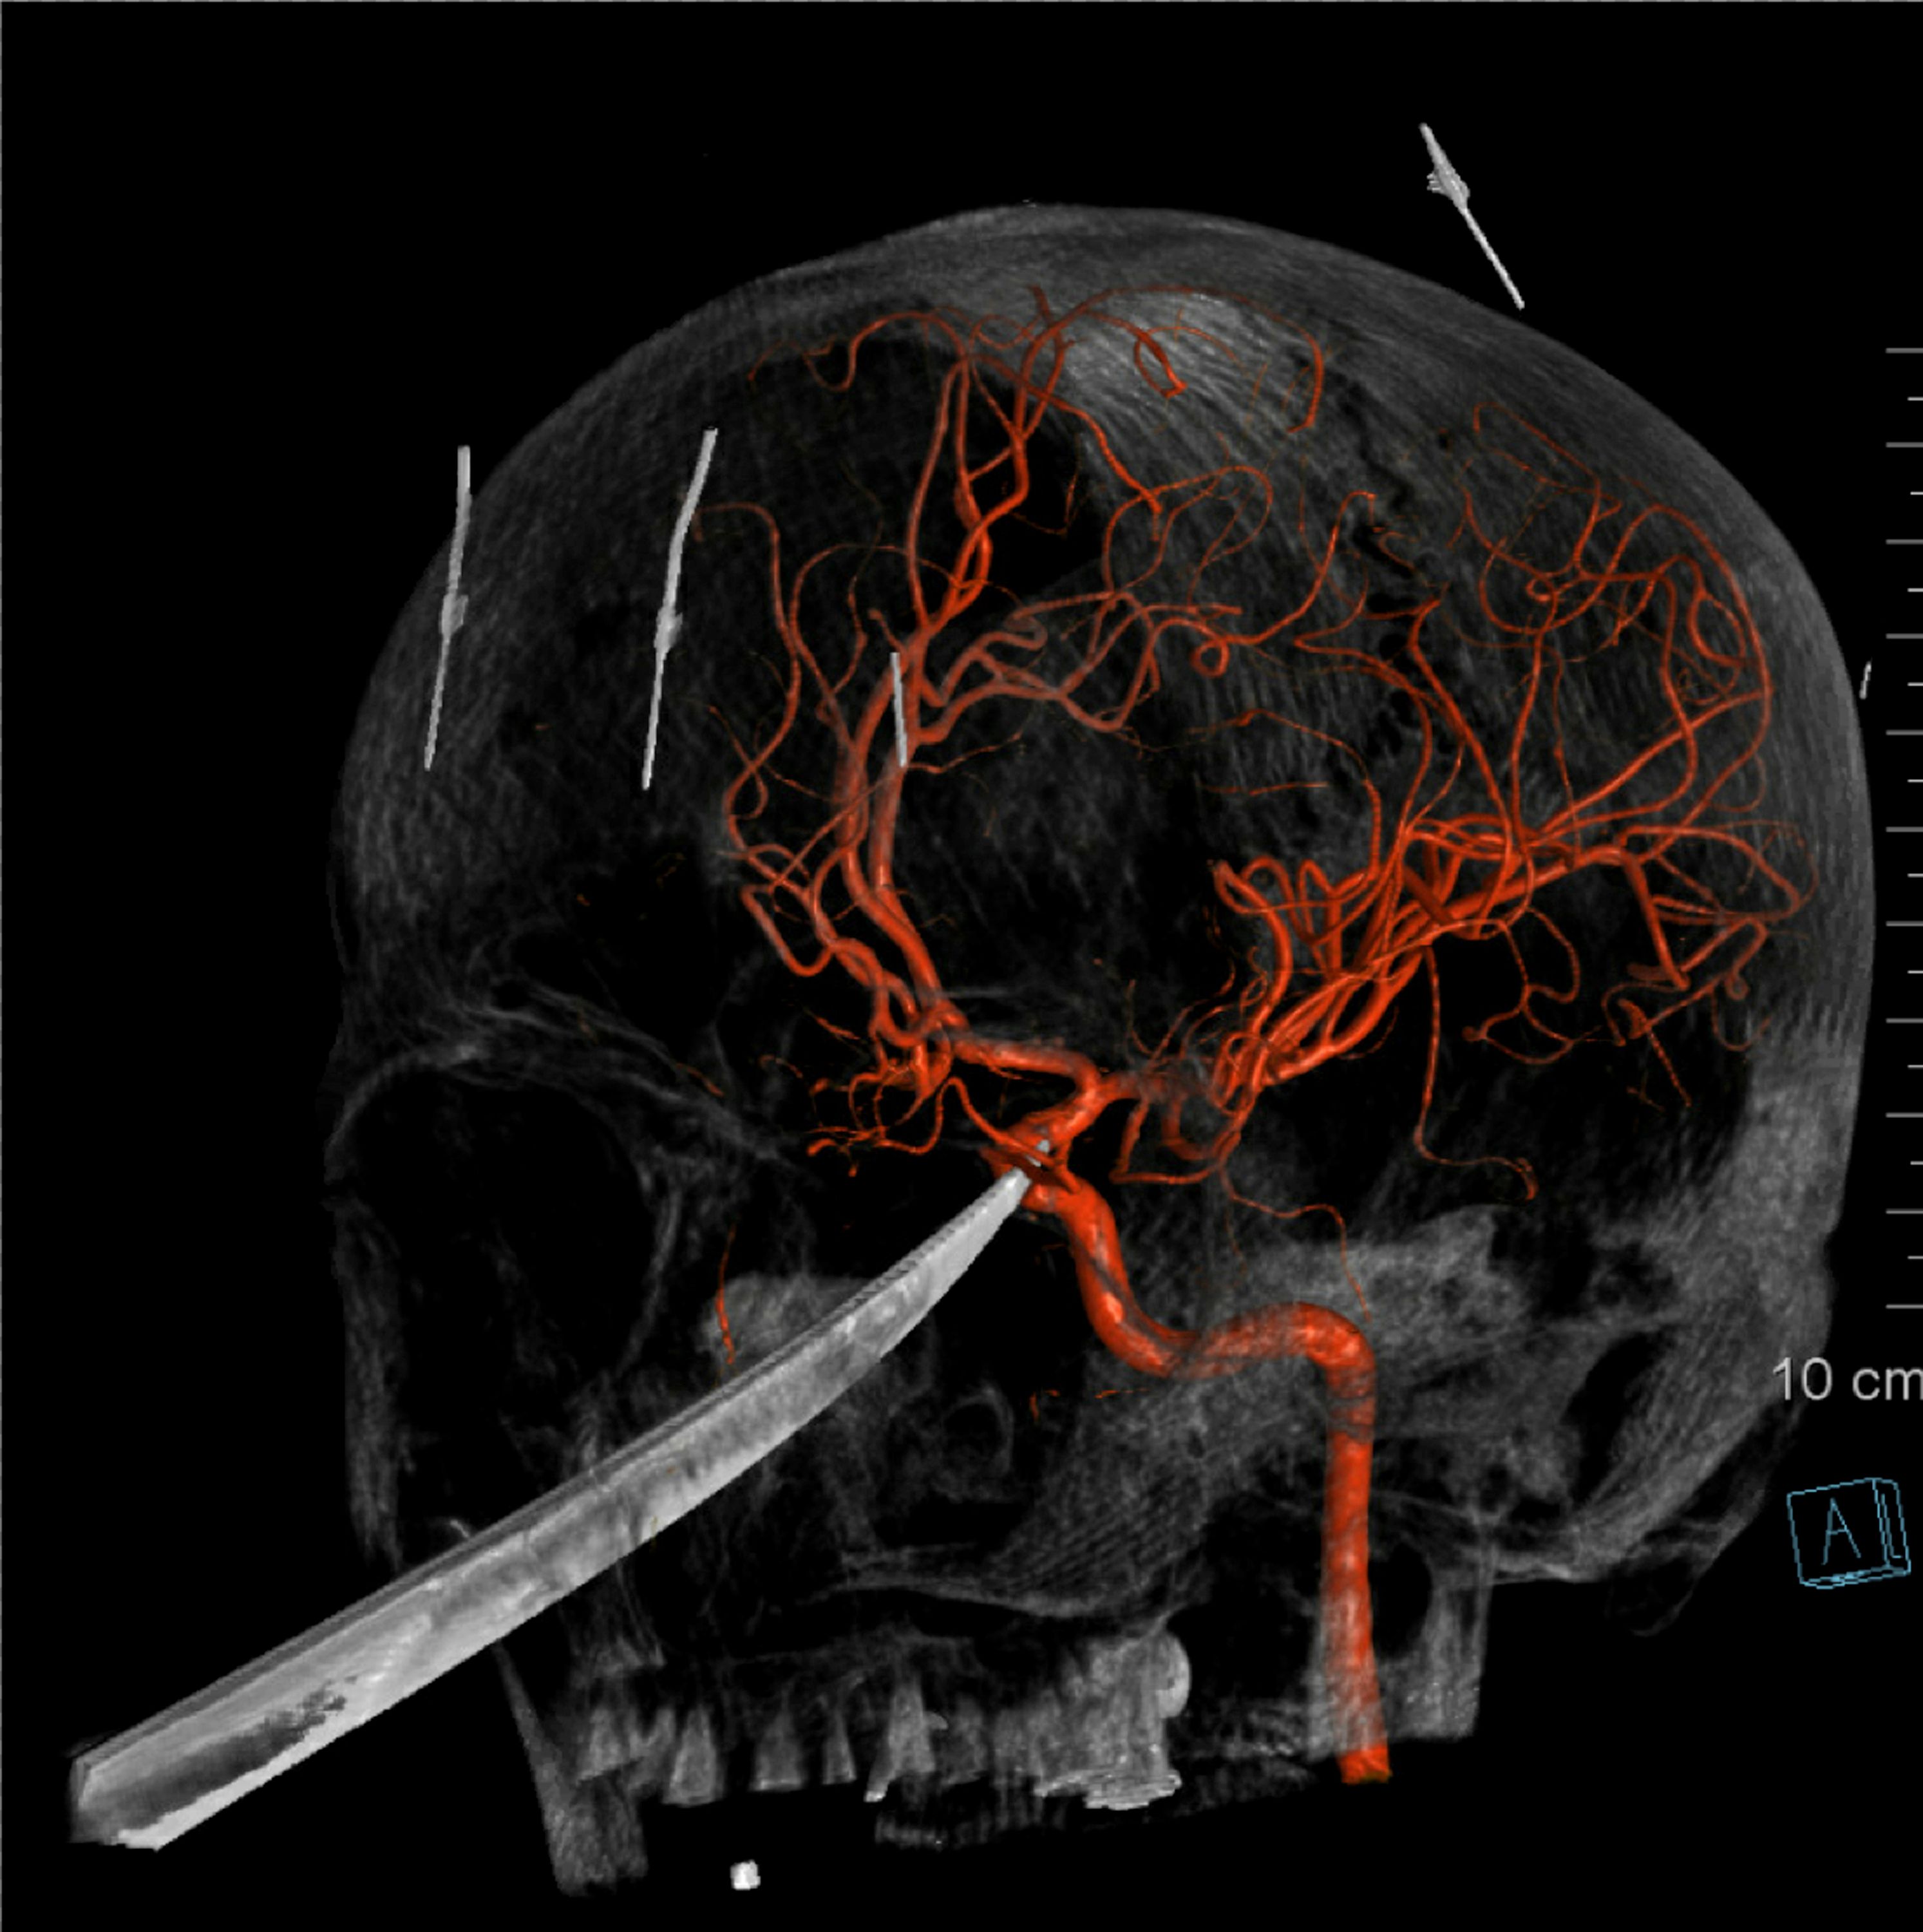

The knife was embedded in his skull and extended to just under his brain. The blade's tip was pushing against his carotid artery, which supplies the brain with blood.

“It could not have had a pound more force on it and him survive that event," said Dr. Koji Ebersole, who oversaw the extraction. “I don't think he would have survived it."

A team of surgeons put together an intricate plan to remove the blade. They were prepared for possible bleeding into the brain, but the operation went without a hitch and the artery remained intact.